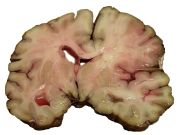

A slice of brain from the autopsy of a person who suffered an acute middle cerebral artery (MCA) stroke

السكتات يمكن تصنيفها في فئتين كبيرتين: قصورية ischemic ونزيفية hemorrhagic.